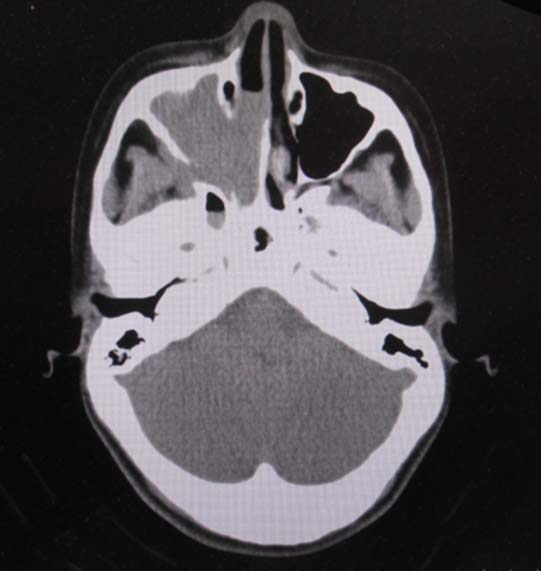

CT所見

副鼻腔腫瘤生検組織

日本病理学会中部支部交見会のスライドより。(S.Suzuki Dr.)

NUT03.jpg NUT04.jpg

詳細は以下のcase reportをご参照ください。

Suzuki S, Kurabe N, Minato H, Ohkubo A, Ohnishi I, Tanioka F, Sugimura H.

A rare Japanese case with a NUT midline carcinoma in the nasal cavity: a case report with immunohistochemical and genetic analyses. Pathol Res Pract. 2014 Jun;210(6):383-8. doi: 10.1016/j.prp.2014.01.013. Epub 2014 Feb 22. PMID:24655834